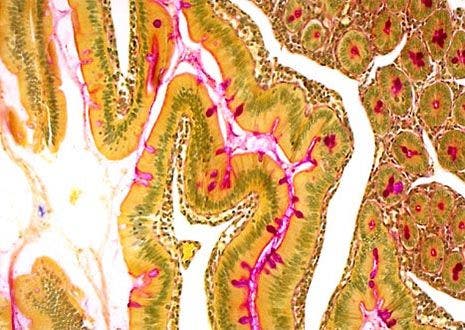

Human Intestinal Tissue

The gut, sometimes referred to as thealimentary canalor thegastrointestinal tract, is approximately nine meters long in the typical human adult. Although metabolism rates differ from person to person, food generally takes 18 to 20 hours to completely pass through the gut.